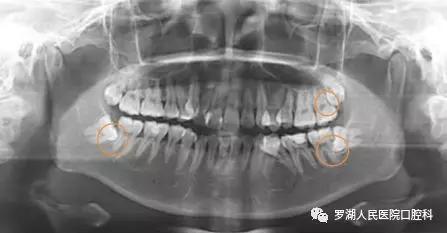

若是智齿本身有龋坏,或引起邻牙龋坏,一般也建议拔除。

当智齿位置不正挤压导致前方第二磨牙龋坏或者牙齿松动,一般建议先行拔除智齿后酌情治疗第二磨牙。